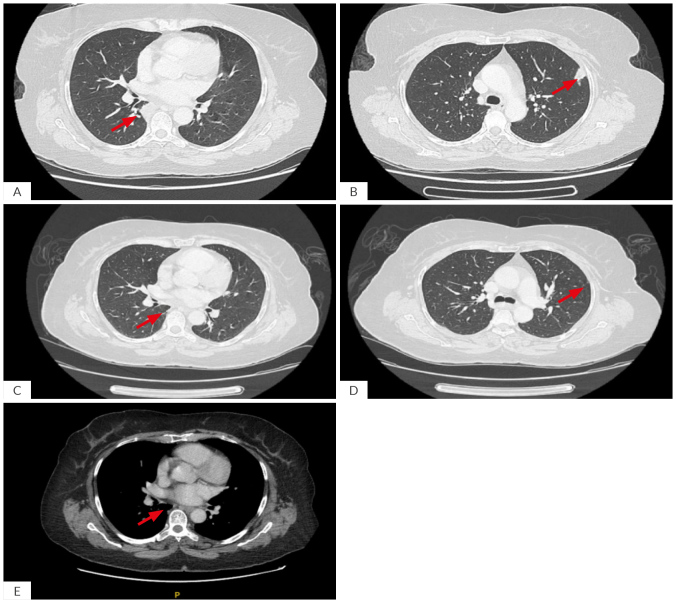

同时出现肺诺卡菌病和肉芽肿病合并多血管炎(GPA)是非常罕见的,并且由于重叠的临床和影像学特征,诊断具有挑战性。我们报告一位54岁女性,有发热、咳嗽、体重减轻和关节痛。胸部影像学示多发肺结节;血清学显示抗中性粒细胞胞浆抗体-蛋白酶3阳性,肺活检显示诺卡菌属坏死性肉芽肿性炎症。这导致肺诺卡菌病和有限型GPA的双重诊断。患者使用复方新诺明后病情有所改善,但由于局限性GPA的表现仍然存在,甲氨蝶呤将在密切监测的同时开始使用。该病例强调了在初步评估疑似血管炎时考虑传染性模拟的重要性,两种实体的双重病理的可能性,以及在控制感染的背景下分阶段治疗此类病例的强调,然后开始免疫抑制治疗。学习要点:肺诺卡菌病在临床和影像学上可能与肉芽肿病合并多血管炎相似,两者很少同时出现。在抗中性粒细胞细胞质抗体阳性患者中,组织病理学检查是区分感染性模拟和血管炎的关键。在开始免疫抑制之前控制感染的分步治疗策略可以降低双重病理并发症的风险。

Concurrent presentation of pulmonary nocardiosis and granulomatosis with polyangiitis (GPA) is exceptionally rare and diagnostically challenging, given the overlapping clinical and radiological features. We report a 54-year-old female with fever, cough, weight loss, and arthralgia. Chest imaging showed multiple pulmonary nodules; serology revealed positive anti-neutrophil cytoplasmic antibodies -proteinase 3, and lung biopsy demonstrated necrotizing granulomatous inflammation with Nocardia species. This led to a dual diagnosis of pulmonary nocardiosis and limited form GPA. The patient improved with co-trimoxazole however methotrexate is set to be initiated concomitantly with close monitoring as the manifestations of limited form GPA were still present. This case highlights the importance of considering infectious mimics during initial evaluation of suspected vasculitis, the possibility of dual pathology of both entities, and the emphasis of the staged approach of treating such cases in the background of controlling infection followed by initiating immunosuppressive therapy.

Learning points: Pulmonary nocardiosis may clinically and radiologically mimic granulomatosis with polyangiitis, and both conditions can rarely present simultaneously.Histopathological examination is crucial to distinguish infectious mimics from vasculitis in anti-neutrophil cytoplasmic antibodies-positive patients.A stepwise treatment strategy in which controlling infection before initiating immunosuppression can reduce the risk of complications in dual pathology.